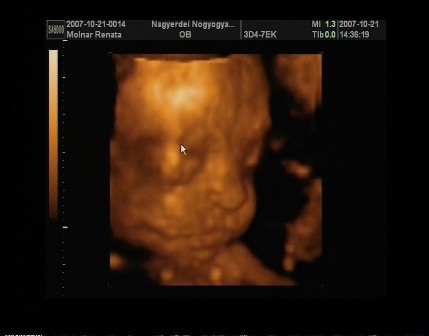

No jöttem beszámolni a pénteki UH-ról. A 4D-s UH végül 2D-s lett,mert a baba fekvése miatt semmi értelme nem lett volna a 4D-s UH-nak.Ugyanis a lelkem harántfekvésben van változatlanul,és a 15perces vizsgálat alatt végig háttal volt nekünk. Pedig nagyon meg lett macerálva és az istennek se akart megfordulni.Doki kb.5percig fel alá járkáltatott hátha felélénkül a drága,de nem...Kellett a bal oldalamra,és a jobb oldalamra is feküdnöm,ám ez sem segített. Finoman ütögette az érzékelőfejjel a hasamat és erre se akart megfordulni.Kis dacos... Ebéd után voltunk UH-on,doki kérdezte is hogy nem-e most ettem,mert baromi higgadt,nyugodt volt a baba,nem nagyon mozgott,és ugyebár meg se fordult.Erre mondtam,hogy igen...kiderült,hogy lehet hogy jobb lett volna ha éhgyomorra megyek,mert akkor élénkebb lett volna.Azt mondta a doki,hogy biztos most ő is jól van lakva,és pihen. A sok macerálás hatására azért háttal nekünk,de elkezdte a kezét,és a lábát emelgetni,meg picit a fejét is.Szegénykémet picit sajnálom,mert nagyon szűk még neki odabent ahogy elnéztem... Ő baromi gyorsan fejlődik,a vizsgálat napján én elvileg 15hetes1napos voltam,de a fejlettségi szintjét nézve a drágám,már akkor 15hetes5naposnak felelt meg. Látszik is,mert baromi pici helyen,teljesen kitölti az egész méhemet!Úgyhogy szerintem hamarosan nagyot fogok pocakosodni...

A csodálatos értékei: a 2 fejkörfogat-->HC: 11.36, BPD: 3.34, pocikörfogata: 9.64(jó nagy már most... ), mellkas körfogata: 2.87, combcsontja: 1.70.